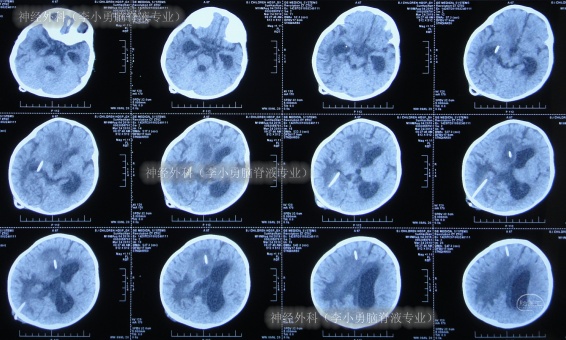

2018年2月9日(第3家医院治疗10天),接受了经右枕侧脑室腹壁外引流术(有分流泵),术后当天查头部CT示引流术后状态(图-5)。

图-5:2018年2月9日头部CT